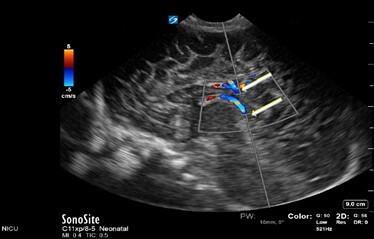

Neonatology Normal Anatomy Too Large Sample Gate Image